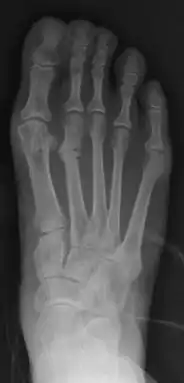

Fraturas por estresse podem ser descritas como pequenas fissuras ou rachaduras no osso;[3] e às vezes são chamadas de "fraturas capilares". As fraturas por estresse ocorrem mais frequentemente em ossos que suportam peso, como a tíbia (osso da parte inferior da perna), metatarsos e ossos naviculares (ossos do pé). Menos comuns são fraturas no fêmur, pelve e sacro.[4]

Radiografias comuns (Rx) frequentemente não detectam a fractura, sendo mais sensível e específico pedir uma tomografia, gamagrafia óssea ou ressonância magnética.[7]